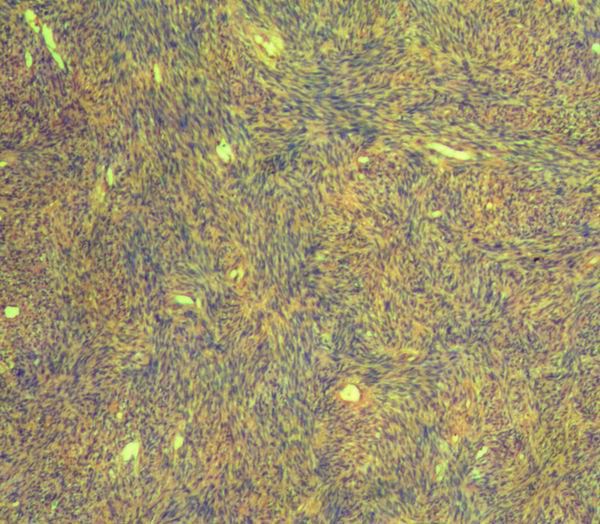

外生殖区平滑肌肿瘤如果诊断平滑肌肉瘤,需把握如下建议的恶性标准((Tavassoli,1979 和Norris, 1979):

需满足下列三个或三个以上条件

(1)肿瘤直径大于5cm;

(2)肿瘤边缘可见侵袭性生长;

(3)核分裂计数大于5个/10HPF;

(4)瘤细胞显示的异型性达到中-高度。

Norris 和Fletcher指出,如果肿瘤内可见凝固性坏死(肿瘤性坏死),只要满足上述四个条件中的任何一条,诊断平滑肌肉瘤将由可能。

外阴部平滑肌肉瘤在男性好发于睾丸、阴茎、精索。在女性,好发于外阴和阴道。

当不能满足上述条件,而具有以下情形的,可诊断为非典型性平滑肌肿瘤(WHO分类将称之为平滑肌肿瘤恶性潜能未定):

(1)肿瘤向边界呈侵袭性生长;

(2)肿瘤细胞具有异型性;

(3)可见核分裂,但核分裂计数达不到上述诊断肉瘤的标准。

本例如果达不到肉瘤标准,可考虑诊断为非典型性平滑肌肿瘤或平滑肌肿瘤恶性潜能未定。